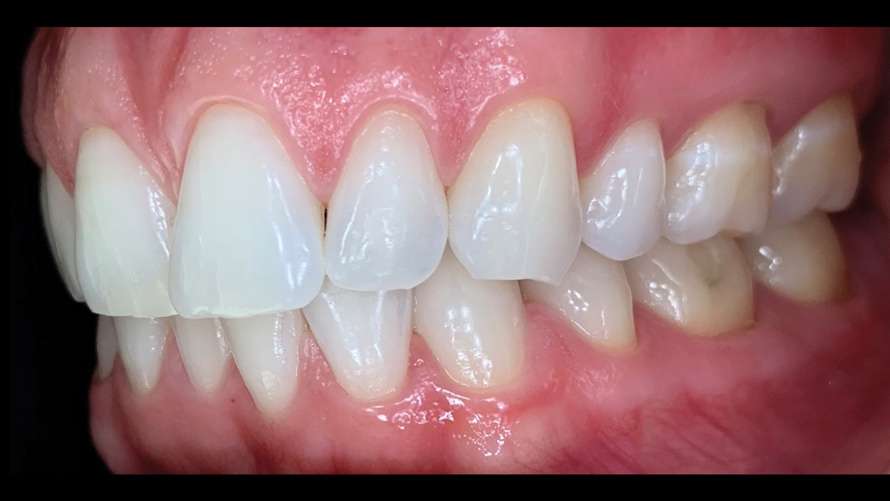

(9.) Preoperative esthetic case documentation using a smartphone and an EALS device.

Figure 9

(10.) Preoperative esthetic case documentation using a smartphone and an EALS device.

Figure 10

(11.) Preoperative esthetic case documentation using a smartphone and an EALS device.

Figure 11